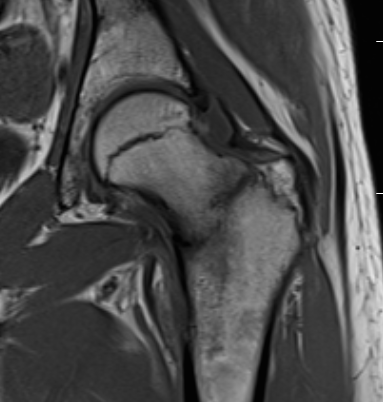

MRI

Edema / fracture line / hip effusion

MRI demonstrating edema likely across entire neck

MRI demonstrates complete fracture